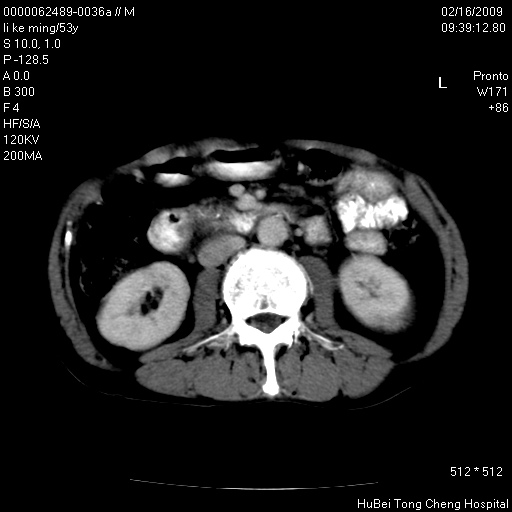

以下是引用卜一在2009-2-16 16:13:00的发言:[br]胰胆管扩张,末端明显狭窄 梗阻,胰头及十二指降段壶腹部结构紊乱。多考虑:十二指降段壶腹部癌!

以下是引用dyqct在2009-2-16 16:58:00的发言:[br]胰头内斑点状及结节状高密度影是钙化灶还是其它?以往做过什么治疗?

以下是引用zsl6918在2009-2-17 8:48:00的发言:[br]符合胰头癌侵犯十二指肠。